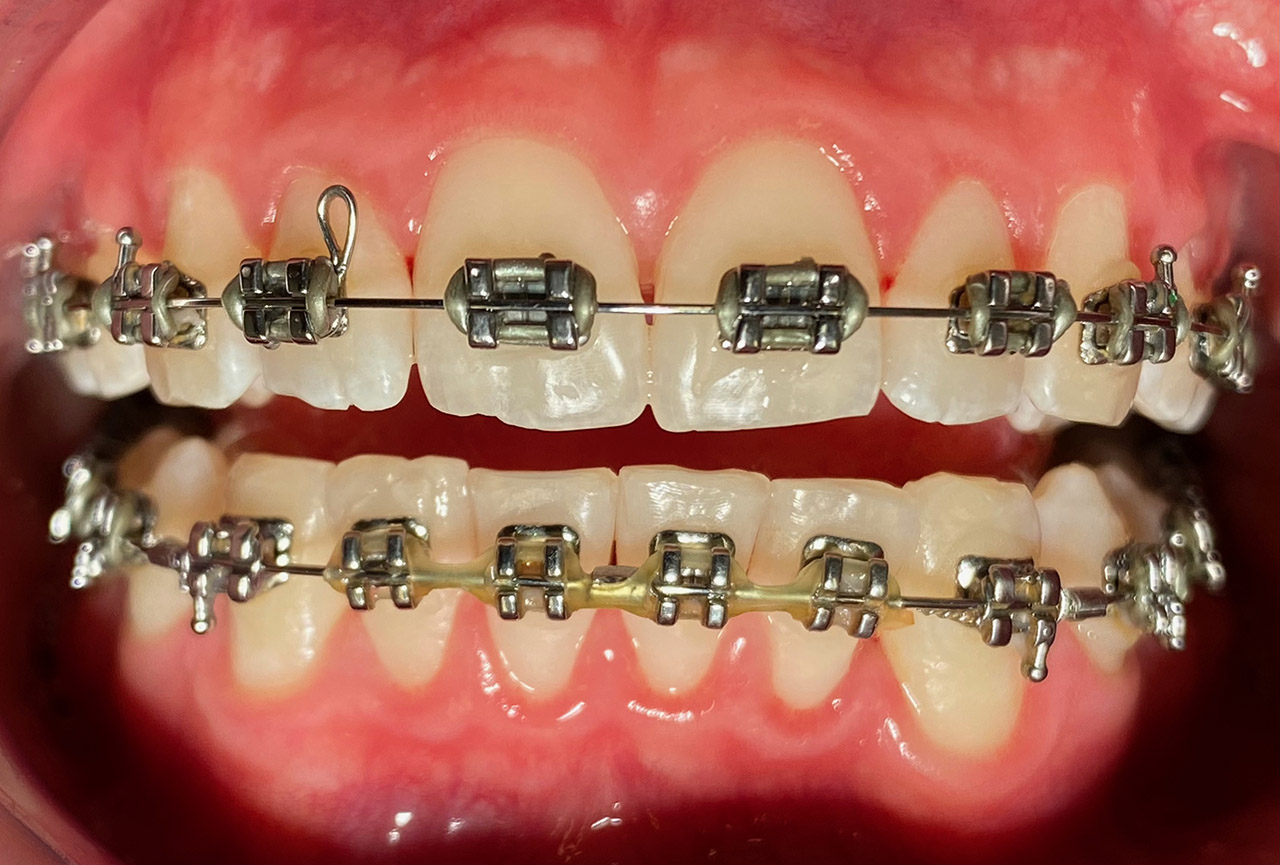

Prophylaxe/professionelle Zahnreinigung:

Zur Motivation, Information und Instruktion einfärben der Beläge (bakterieller Biofilm) bei jungem Patienten in kieferorthopädischer Behandlung. Reinigung der Zähne mit Pulverstrahltechnik minimalinvasiv und zahnschonend und wo noch nötig gezielt mit Ultraschall.

Das Resultat 45 Minuten später.